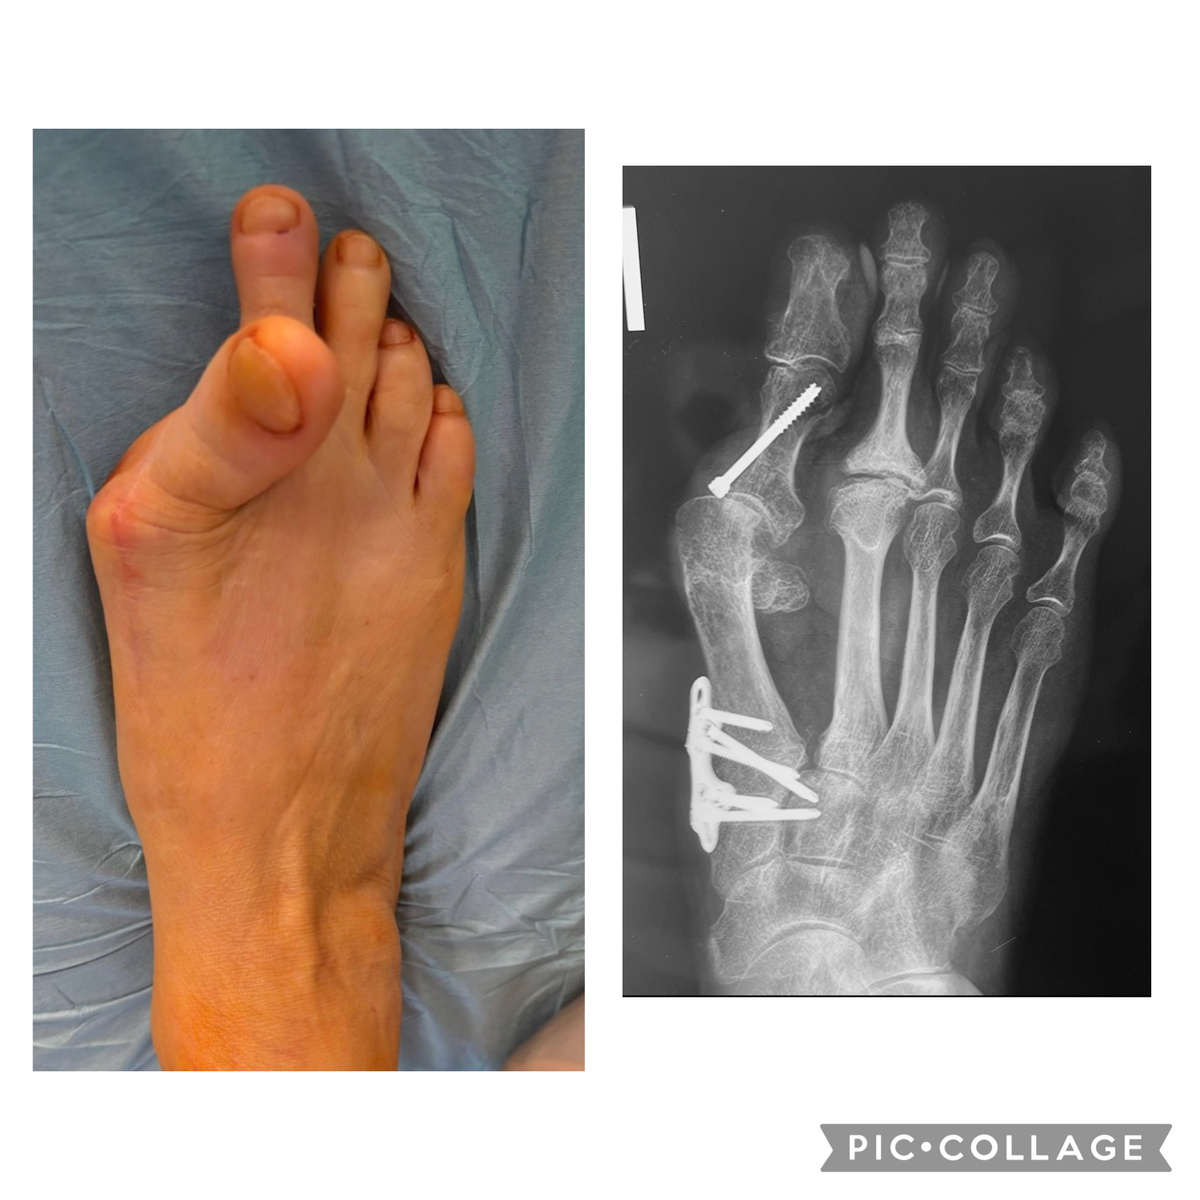

Вот пример.

-2

Так это выглядело на момент моей операции. Несмотря на внешний ужас-ужас, на самом деле всё не так плохо.

-3

Буквально час работы, и готово. Максимум возможного. Осталось дело за малым - дождаться, пока всё заживёт. Кости, мягкие ткани. На этот счёт мы даём чёткие рекомендации - когда, куда, зачем, как и т.д. Выписываем домой в функциональной повязке, которую рекомендуем не трогать, а лучше - через 7 и 14 дней приехать на перевязку и снятие швов. Для Москвы и Подмосковья это не проблема. Кроме того, настоятельно советуем ходить поменьше, держать ногу большую часть времени горизонтально.